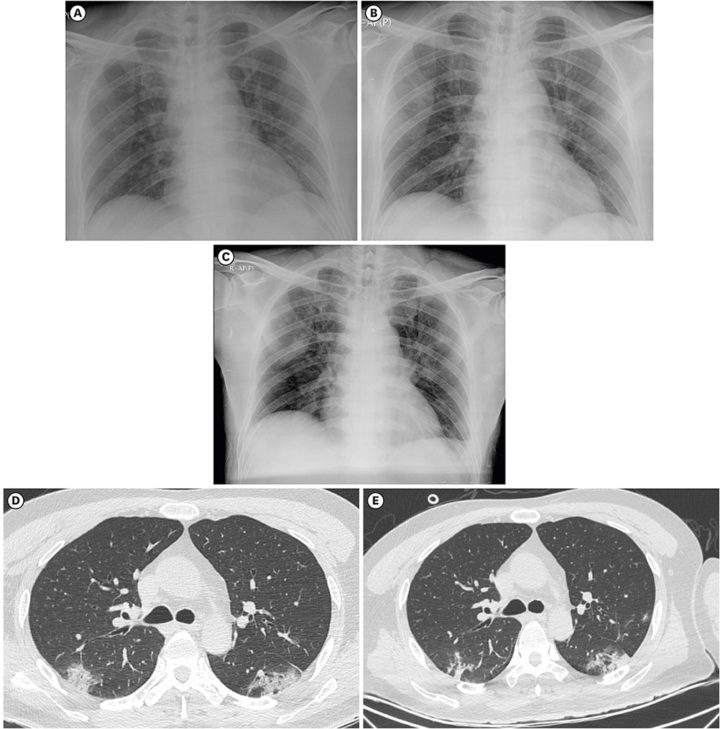

Ed è guardando alle lastre radiologiche effettuate sui pazienti di quei numerosi casi di polmonite di novembre e di dicembre 2019 che, si possono osservare sull’apparato respiratorio analoghi impatti a quelli verificati nei casi ufficiali di pazienti con polmonite da Covid-19.

Radiografie a confronto di pazienti affetti da polmoniti virali da Covid-19